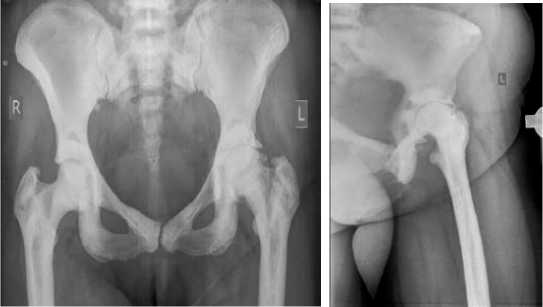

На 1-е сутки после операции выполнены контрольные рентгенологические исследования (Рис. 2), активизация пациентки при помощи костылей.

Рисунок 2. Контрольная рентгенография после оперативного вмешательства

Течение раннего послеоперационного периода без особенностей. Выписка из стационара на 6-е сутки после оперативного вмешательства. На амбулаторном этапе проводилось наблюдение пациентки на сроке 1,3 месяцев. Пациентка передвигается самостоятельно, дополнительную опору не использует, жалоб нет.